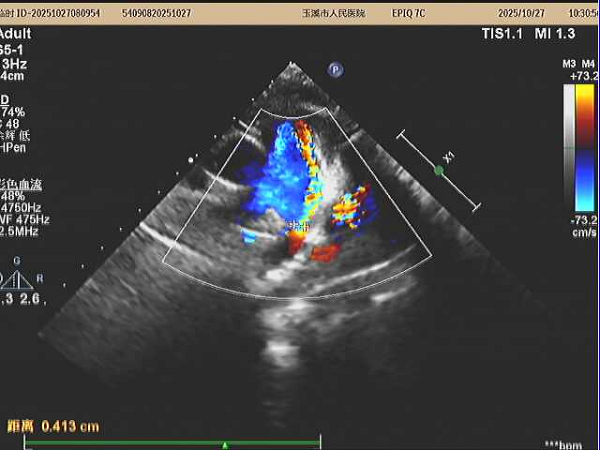

在张智伟教授指导下,玉溪市人民医院心内科团队手术过程中,精准定位动脉导管分流位置,将生物可降解封堵器成功植入,实现了对分流的有效封堵。术后超声评估封堵器周围无残余分流,封堵器占位良好。